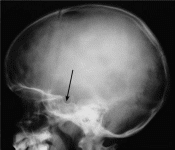

Рентгенологические исследования. Для диагностики патологии гипофиза долгие годы применялась рентгенография черепа в прямой и боковой проекциях, прицельная рентгенограмма, томограмма, на которых изучалось состояние турецкого седла, которое является костным ложем гипофиза. На рентгенограммах оценивают форму седла, состояние передней стенки, дна и спинки, сагиттальный и вертикальный размеры. Размеры и форма турецкого седла вариабельны.

Рисунок Рентгенограмма черепа в боковой проекции (стрелка – турецкое седло), прицельная рентгенограмма турецкого седла